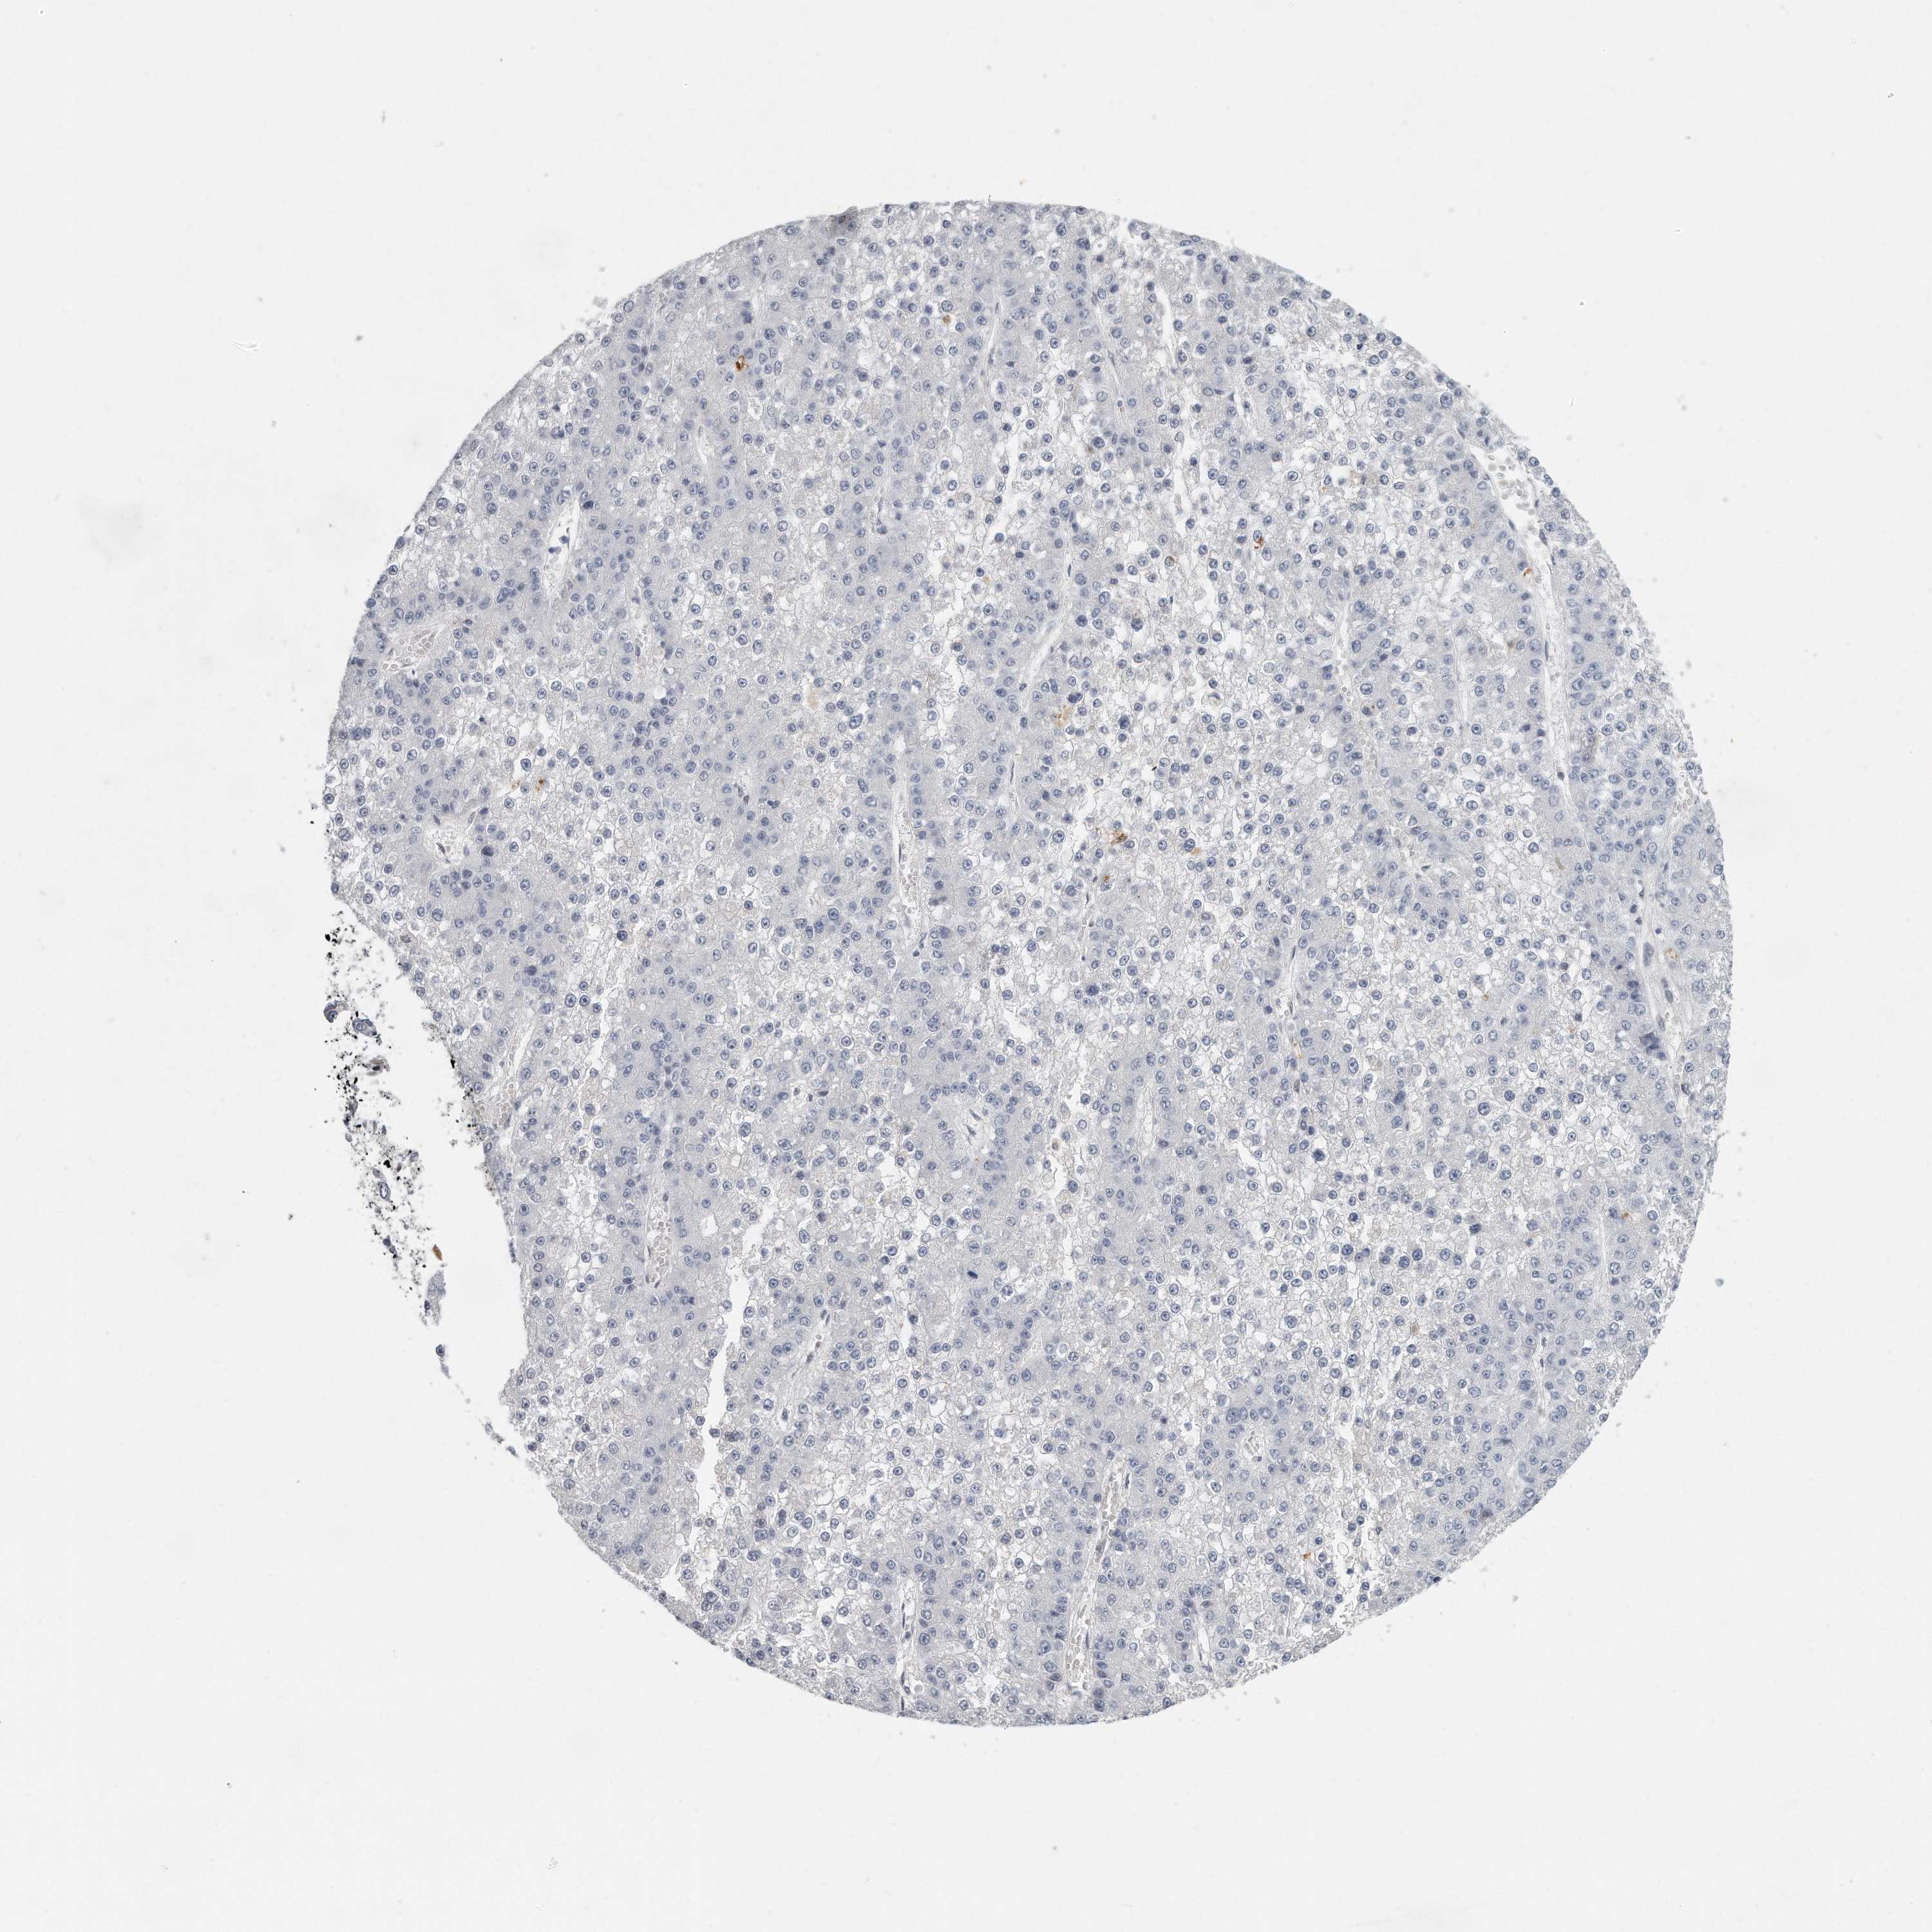

LIVER CANCER - Protein expressioni

A mouse-over function shows sample information and annotation data. Click on an image to view it in a full screen mode. Samples can be filtered based on level of antibody staining by selecting one or several of the following categories: high, medium, low and not detected. The assay and annotation is described here.

Note that samples used for immunohistochemistry by the Human Protein Atlas do not correspond to samples in the TCGA dataset.

Antibody stainingi

Antibody staining in the annotated cell types in the current human tissue is reported as not detected, low, medium, or high, based on conventional immunohistochemistry profiling in selected tissues. This score is based on the combination of the staining intensity and fraction of stained cells.

Each image is clickable and will lead to virtual microscopy that enables deeper exploration of all samples and also displays staining intensity scores, fraction scores and subcellular localization as well as patient and tissue information for each sample.

Antibody HPA023559

Antibody HPA023564

Antibody HPA044971

Antibody CAB031916

Staining

High

Medium

Low

Not detected

Intensity

Strong

Moderate

Weak

Negative

Quantity

>75%

75%-25%

<25%

None

Location

Nuclear

Cytoplasmic/membranous

Cytoplasmic/membranous,nuclear

Cholangiocarcinoma

Carcinoma, Hepatocellular, NOS